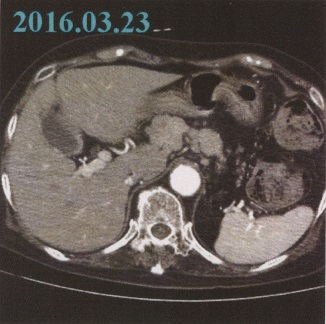

3月26日(土) 高瀬医師より、定例の検査報告である。

「先ず、腹部リンパ節の状態は先月より更に小さくなっているのが見て取れます。このような経緯から推察すると、やはり、腺がんと(奈良井病院で)言われた当初の診断そのものが疑わしく思われるほど落ち着いています。

それに対し、脳腫瘍の長径は6㎝その周辺に浮腫みも出てきており、脳梁(のうりょう)体側部への広がりも認められます。

但し、脳動脈の閉塞は見られません。今後起こりうる病態としては、広範囲脳梗塞や腫瘍からの出血などが懸念され、それが一旦起きれば、急激な意識障害・呼吸および心停止につながる恐れもあります。ですから、向後(こうご)のリハビリ実施や息子さんがやるマッサージについては、特に細心の注意が要されますので気をつけてください」

言語・運動能力の衰えや食欲減退も、つまりは脳腫瘍の肥大によるもの。諸事、先が思いやられる……。(つづく)